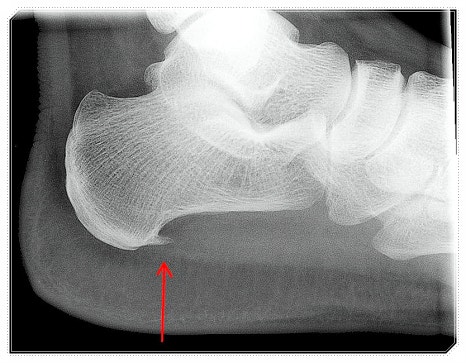

족저근막염이나 발뒤꿈치 통증처럼 흔한 족부 질환도, 대부분은 이렇게 참고 지낸 시간이 길어지며 만성으로 이어지는 경우가 많습니다.

오늘은 아침에 유독 심해지는 발뒤꿈치 통증의 진짜 원인이 무엇인지, 왜 그런 현상이 생기는지에 대해 차분히 이야기해 보려 합니다.